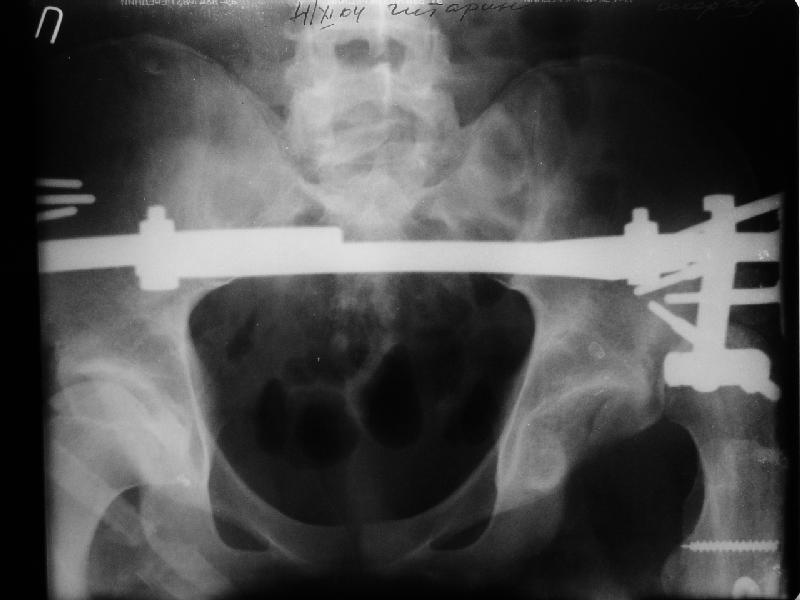

Уважаемые коллеги,пожалуйста, подумайте над следующим ребусом. В нашу клинику поступилпациент из области, 17лет, получивший травму в ДТП 25.08.04, открытый перелом бедра, при поступлении наложено скелетное вытяжение.

30.09.04 на операции выявлен вывих бедра и перелом голени на этой же стороне. Остесинтез бедра все же выполнен, и по заживлении раны пациент переведен к нам. Кроме того у пациента нейропатия седалищного нерва на этой же стороне. В нашей клинике планируется наложение аппарата таз-бедро, для постепенного низведения бедра с последующим открытым вправлением, замена фиксатора на запираемый гвоздь и блокируемый остесинтез голени. Вариант с первичным эндопротезированием мы не рассматривали из-за юного возраста пациента. Вопрос с чего начать? Кроме того, сгибание в коленном суставе в настоящее время (95 градусов) затрудняет остеосинтез голени.Стоит-ли менять гвоздь? Или же спилить торчащий конец во время открытого вправления? Может, попробовать все сделать одномоментно? Заранее спасибо.

На мой взгляд, на ренгенограмме таза (левый сустав) имеется (имелось) перелом заднего края вертлужной впадины, перелом ацетабулум-вывих головки? (нужны дополнительные снимки).

если проследить две линии: передний и задние края ацетабулум должны встречатmся с латеральной стороны ацетабулум, а у данного больного они формирует цифру "8", т.е. передний край ацетабулум расположен более спереди. Ацетабулум у этого больного немного в ретроверсии, т.е. задний край у него недоразвит и трудно удержать головку в cуставе после реконструкции.

Просьба простить за длительное молчание, не было фотоаппарата, чтобы перенести рентгенограммы. Больного прооперировали в прошлый четверг, как и предполагали, голень проблем не доставила(настолько, что даже не ввели дистальные винты по ряду причин: срок после травмы, целая малоберцовая, последующая длительная ходьба без нагрузки, да и гвоздь сел плотно). Изначально планировали после удаления фиксатора антеградно завести стержень и утопить конец, но вопрос был исчерпан, когда выяснилось, что все имеющиеся стержни слишком длинные, пришлось ретроградно забить большеберцовый гвоздь, после рассверливания; серьезные проблемы возникли с устранением ротации. В вертельной области сломали стержень-джойстик(привет установщику эндопротеза), дальнейшие манипуляции проводили пучком спиц и стержнем с кондуктором. Закончили все аппаратом таз-бедро. Решили что возможные огрехи с ротацией устраним после открытого вправления. Снимки прилагаю. Спасибо за участие в обсуждении. Обязуюсь информировать о дальнейших этапах лечения.